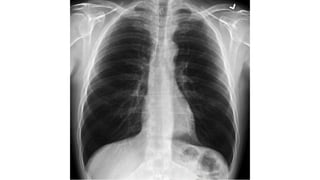

CHEST X RAY (CXR) Check for..

A – airways

B – basal lungs & pleura

C – cardio mediastinum

D – disabilities (visible fractures etc)

E – everything else

• R > L diaphragm gap (not more than 3cm)

• Cardiothoracic ratio not more than <55%

• Trachea diameter < 25mm in males/ < 21mm in females.

• Aortic notch should be visible.

• Any gastric abnormalities (bubbles)

CHEST X RAY(CXR) Check for.. A – airways B – basal lungs & pleura C – cardio mediastinum D – disabilities (visible fractures etc) E – everything else • R > L diaphragm gap (not more than 3cm) • Cardiothoracic ratio not more than <55% • Trachea diameter < 25mm in males/ < 21mm in females. • Aortic notch should be visible. • Any gastric abnormalities (bubbles)